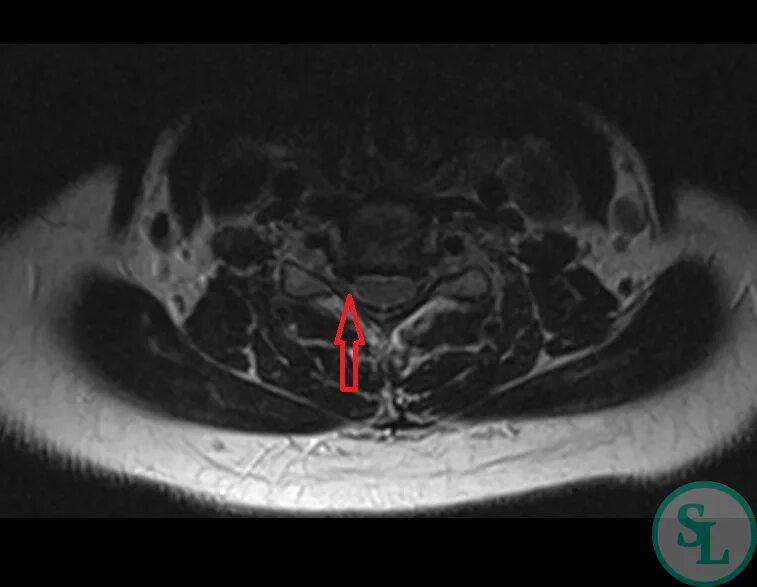

Можно ли вылечить грыжи шейные